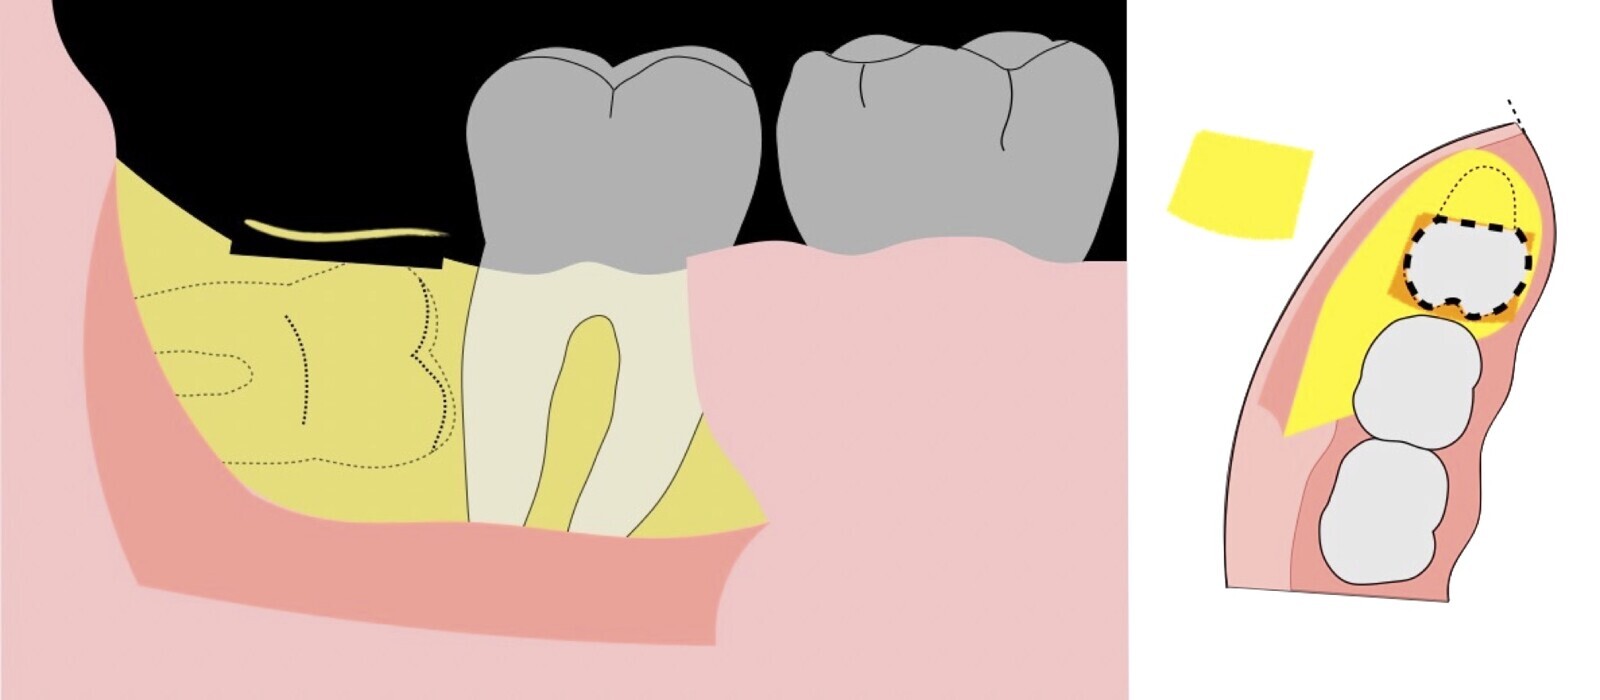

El procedimiento se inicia colocando anestesia troncular para bloqueo del nervio dentario inferior y sus ramas. Luego, se establecerá el diseño de acceso según la disposición de la molar a extraer. Para fines didácticos, se explicará cómo se realizaría la extracción de la molar de la Figura 1: se realiza una incisión horizontal a nivel de la zona retromolar hasta llegar a distal de la segunda molar, continuándose con una incisión intrasurcular hasta mesial de la segunda molar, finalizando con una incisión vertical a espesor total hasta llegar a la línea mucogingival (Figura 2).

Figura 2. Diseño de incisión para el acceso a la tercera molar.

Figura 3. Decolado a espesor total para el acceso a la tercera molar.